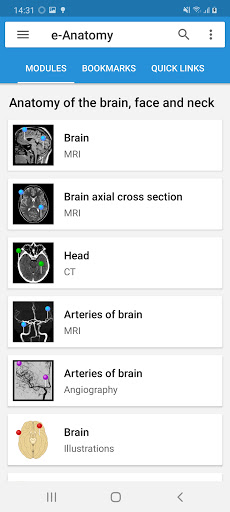

- وحدتان جديدتان: الدماغ - TOF والأوعية الدموية الدماغية ، أطلس التشريح الوعائي العصبي الطبيعي لشرايين الدماغ على الأوعية الدموية الدماغية. - تم إعادة صياغة الواجهة. - تتوفر علامة تبويب جديدة باسم "QuickLinks" ، ترسل وحدات في أقسام من جسم الإنسان وتسمح لك بالسفر السريع إلى الوحدات التي تبحث عنها. الخلل الصغيرة الثابتة.